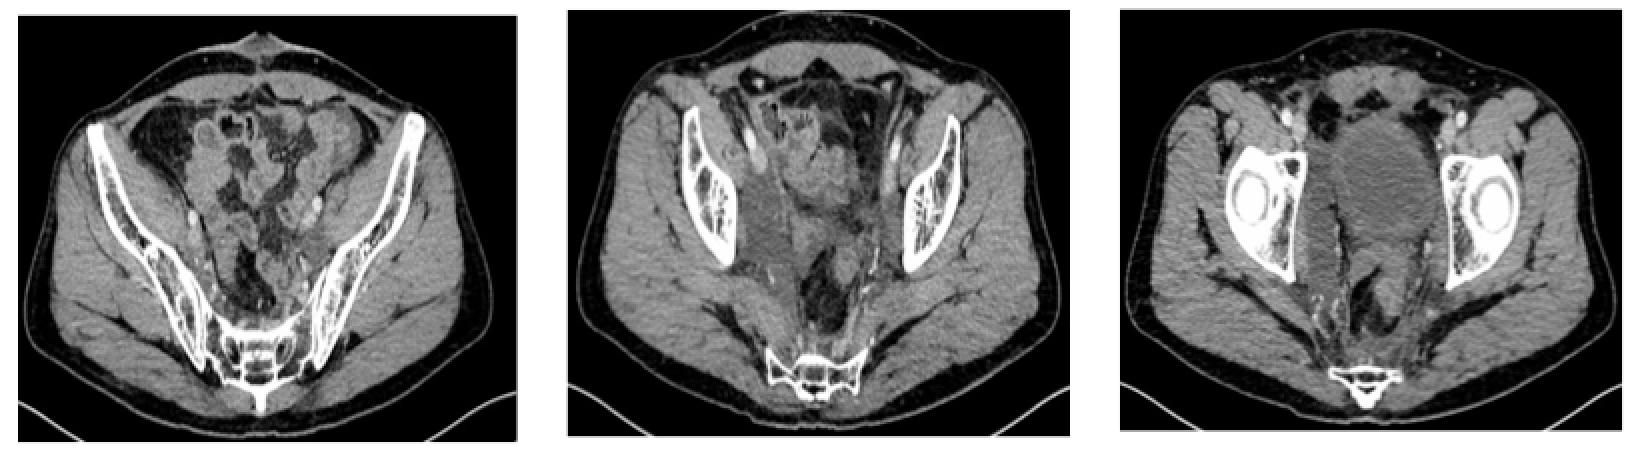

全腹CT

直肠中下段肠壁增厚,考虑直肠癌,伴直肠周围间隙、直肠旁间隙、双侧髂血管旁淋巴结增多、增大,请结合临床及其他检查。

左侧肾上腺结节,转移?腺瘤?或其他?左肾前下份轮廓欠光整,慢性炎症改变?左肾小囊肿。

肝右后叶上段钙化灶

疗效评估(同步放化疗结束时,2017.2.14):SD

直肠中下段肠壁增厚,考虑直肠癌,伴直肠周围间隙、直肠旁间隙、双侧髂血管旁淋巴结增多、增大,与2016-12-2日旧片比较,左侧髂血管旁淋巴结略缩小,其余未见明显变化,请结合临床及其他检查。

左侧肾上腺结节,转移?腺瘤?或其他?与上述旧片比较未见明显变化。

左肾前下份轮廓欠光整,慢性炎症改变?左肾小囊肿。

肝右后叶上段钙化灶。

前列腺钙化灶。

疗效评估(2017.4.26):PR?

直肠中下段肠壁增厚,考虑直肠癌,伴直肠周围间隙、直肠旁间隙、双侧髂血管旁淋巴结增多、增大,与2017-02-14日旧片比较,直肠壁增厚较前减轻,其余未见明显变化,请结合临床及其他检查。